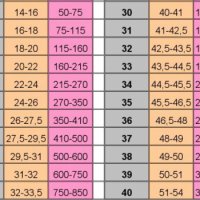

ТАБЛИЦЯ Про ПРОЦЕСІ ВАГІТНОСТІ